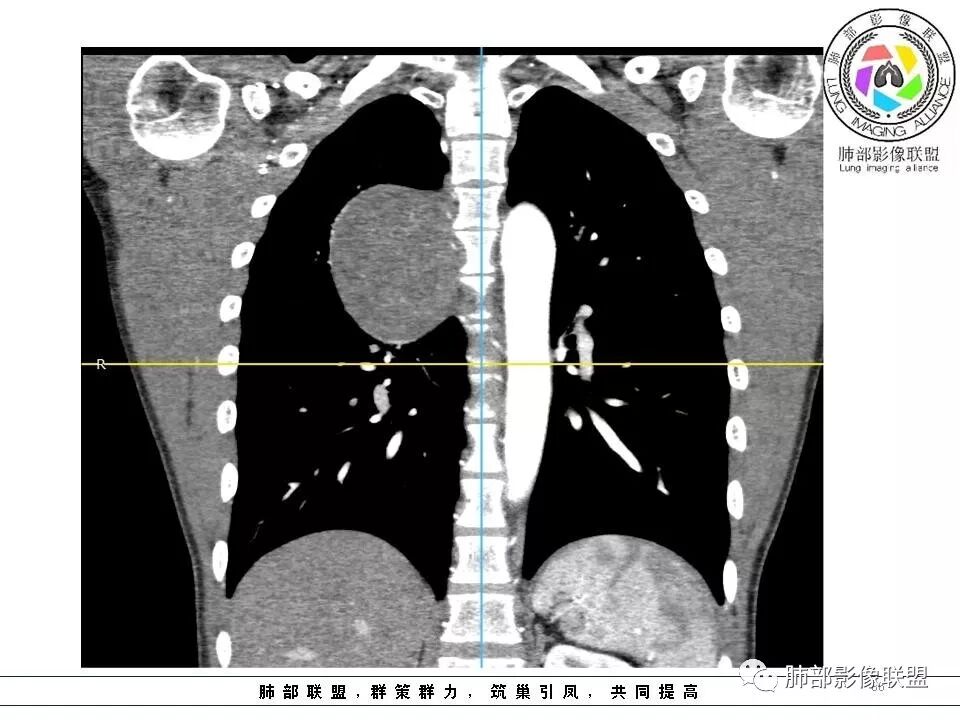

右后纵膈脊柱旁软组织占位,形态规则类圆,边缘光整,肺组织受压,胸膜尾,肋间动脉供血。中度不均匀延迟强化。

后纵隔脊柱旁占位性病变,疾病谱有神经鞘瘤,sft,节细胞瘤,髓外造血。此例有胸膜尾征,蛇纹征 ,延迟强化。考虑胸膜孤立性纤维瘤。看到有供血动脉,但不知道是哪里的血管。

后纵隔类圆形新生物,边缘光滑,胸膜尾征明显,贴近脊柱,蛇纹,血供丰富,考虑后纵隔软组织肿瘤,具体类型看不出来,鉴别神经鞘瘤。

右后纵膈脊柱旁软组织占位,边界清晰,光整,肺组织受压。胸膜被掀起,肋间动脉供血,中度不均匀延迟强化。考虑神经鞘瘤,不除外纤维瘤

右后纵膈脊柱旁软组织影,与纵隔结构分界不清,形态规则类圆,边缘光整,肺组织受压,胸膜尾,肋间动脉供血。肺动脉推移,中度不均匀延迟强化。考虑神经来源,神经鞘瘤,神经纤维瘤二者不易鉴别。

青年男性,间断胸痛;右侧脊柱旁可见一类圆形软组织密度影,密度欠均匀,增强扫描呈轻中度持续强化,邻近肺组织及肺动脉推移,可见肋间动脉供血,部分胸膜下脂肪可见,部分层面似见与右侧椎间孔相连。考虑后纵隔神经源性肿瘤。

后纵隔脊柱旁占位性病变,有胸膜尾征,胸膜下脂肪可见,蛇纹征,明显强化。考虑孤立性纤维瘤。

边缘光滑,宽基底与胸壁相连,跨叶裂,叶裂稍前推,血管、支气管前移。

浅分叶

外上侧少量胸水

肋间动脉供血,强化尚均匀,逐步强化

1.右上胸内脊柱旁类圆形肿块,质地似乎比较坚实,密度稍显不均,但未显示明确的坏死。

如此密度形态的病灶位于肺边缘首先应当想到孤立性纤维瘤,可相邻胸膜未见明显的异常强化和胸膜方向延伸。

2.肋间动脉病供血也提示肿块来自后纵隔?